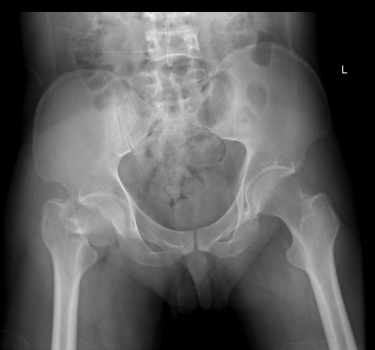

术前X线片

2015年12月,一名32岁的青年男性工作时不慎从高处坠落导致股骨颈骨折(经颈型)而入住我院骨创伤与手外科,考虑该类骨折具有很高的坏死率,患者越年轻坏死率越高。“以往,该类骨折手术的实施主要依靠患者的X光片进行手术分型,但X光片的缺陷主要在于其平面化,因此往往需要医生有一个立体空间的想象力,才能为接下来的手术做好铺垫。”即使行局部骨折三维重建也难以让手术医师有个直观的感觉,无法在体外对其进行术前预演。因患者体重较肥胖,骨折移位明显,为降低患者的股骨头坏死率的发生,科室主任陈跃平教授提出使用3D打印技术的“提前干预”,通过3D打印出他的全仿真患者股骨颈进行手术预演,因为有了预演的经验,最终手术得以精准、迅速完成,耗时较以往少了一半以上,目前创伤骨科已为近10位患者成功实施手术,患者术后恢复良好。